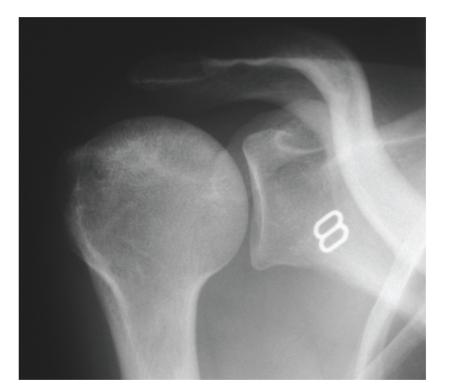

Sickle cell anaemia is an autosomal recessive genetic condition producing abnormal haemoglobin HbS molecules that result in stiff and sticky red blood cells leading to unpredictable episodes of microvascular occlusions. The clinical and radiological manifestations of sickle cell anaemia result from small vessel occlusion, leading to tissue ischemia/infarction and progressive end-organ damage. In this paper we discuss and illustrate the various musculoskeletal manifestations of sickle cell disease focusing primarily on marrow hyperplasia, osteomyelitis and septic arthritis, medullary and epiphyseal bone infarcts, growth defects, and soft tissue changes.

镰状细胞贫血是一种常染色体隐性遗传疾病,会产生异常的血红蛋白HbS分子,导致红细胞僵硬且黏附性增强,从而引发不可预测的微血管闭塞发作。镰状细胞贫血的临床和放射学表现是由小血管闭塞引起的,会导致组织缺血/梗死以及终末器官的进行性损害。在本文中,我们将讨论并举例说明镰状细胞病的各种肌肉骨骼表现,主要聚焦于骨髓增生、骨髓炎和化脓性关节炎、骨髓和骨骺骨梗死、生长缺陷以及软组织变化。